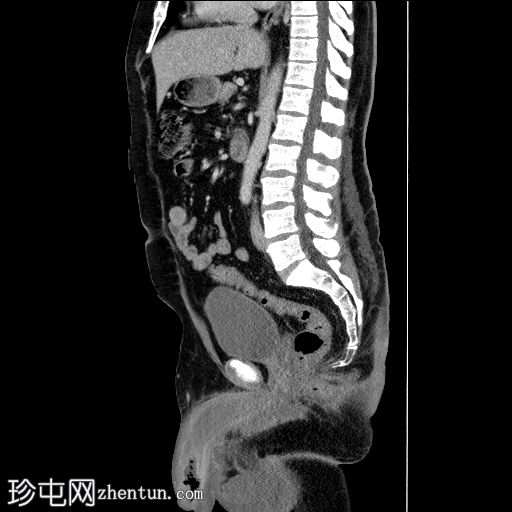

矢状位增强扫描(门静脉期)

弥漫性阴茎水肿,阴茎海绵体内积液伴气体,腹股沟淋巴结肿大。

患者既往有阴茎感染史,已行手术治疗。由于阴茎血供丰富,孤立性阴茎坏疽较为罕见。通常情况下,阴茎海绵体不受累,但本例累及阴茎海绵体、龟头和尿道。若无外伤史,可能需要行腹部影像学检查以排除胃肠道感染。本病例也强调了在血尿患者中进行腹部影像检查时,应将整个阴茎体纳入检查范围的重要性。作为一种危及生命的突发性泌尿外科急症,早期识别和治疗将影响患者的预后。